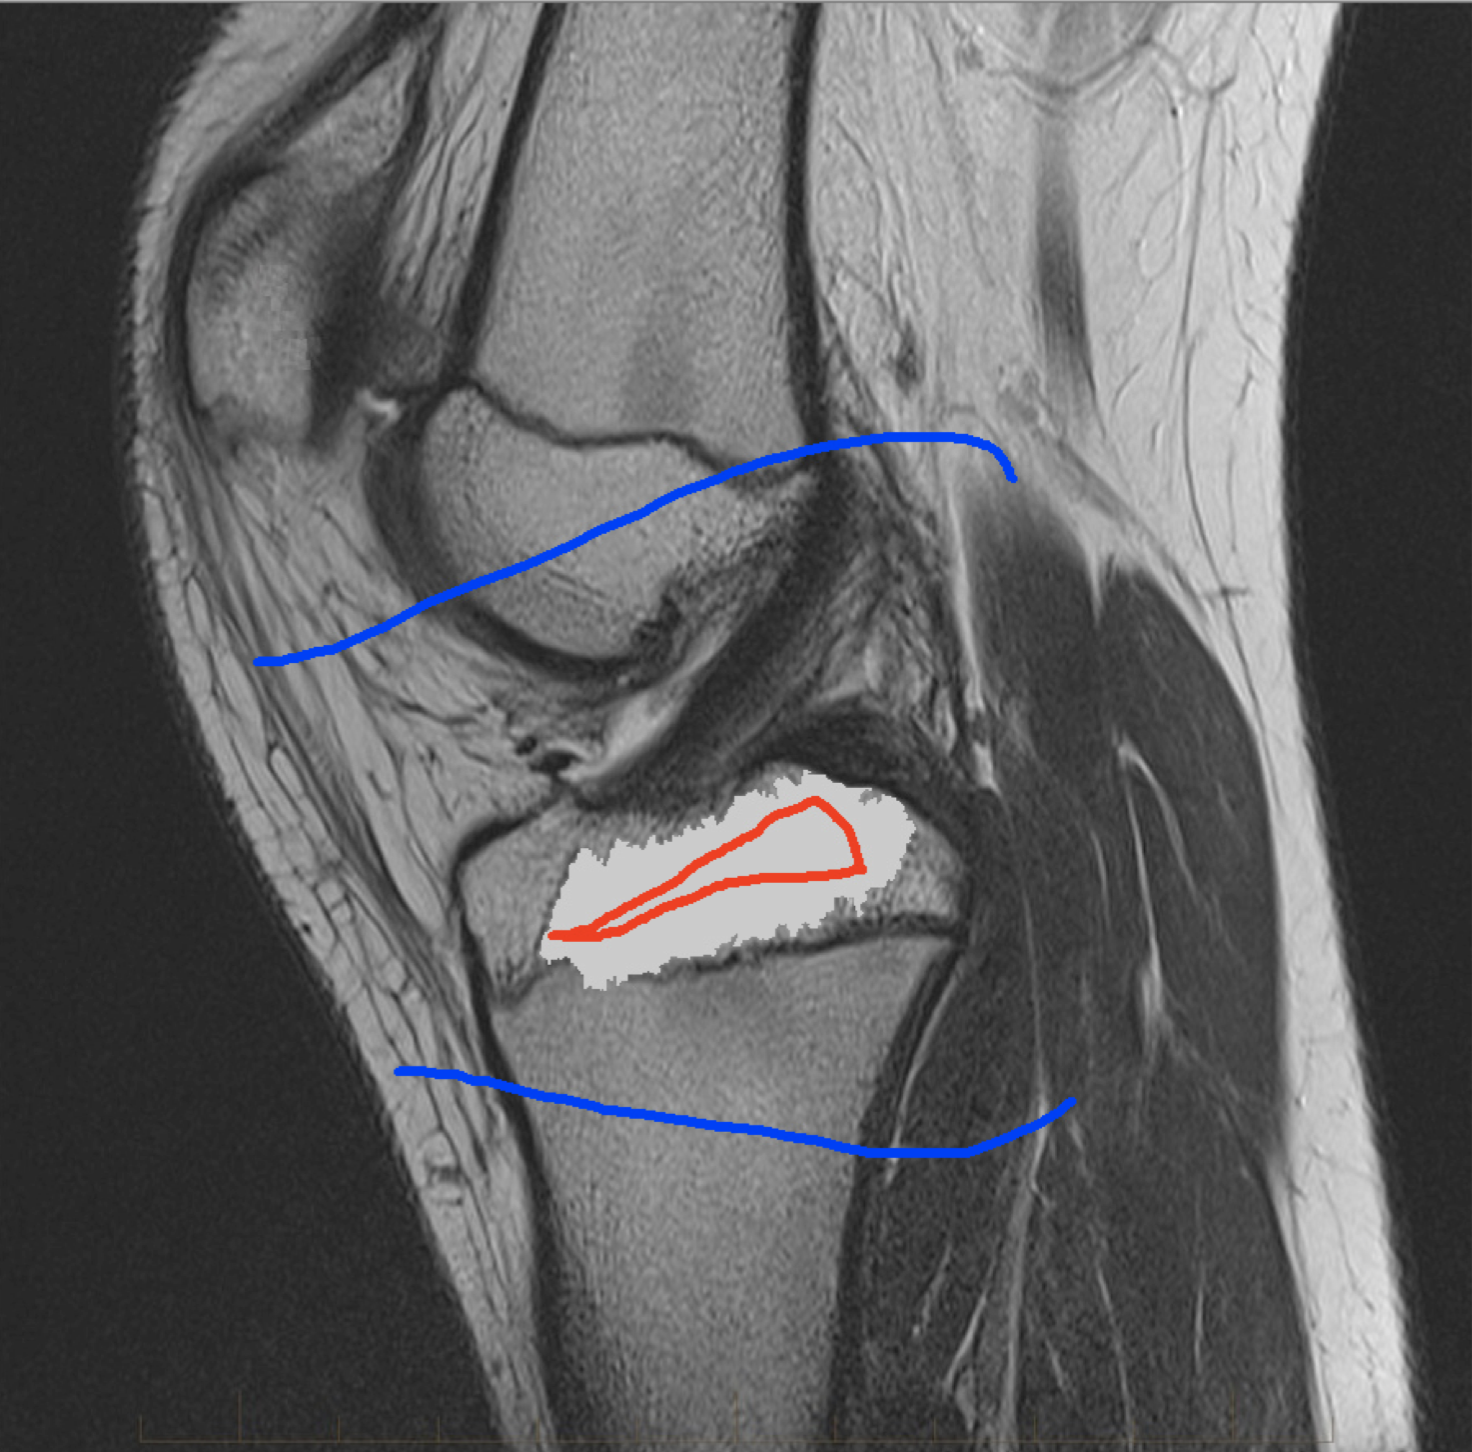

Four sets of test results are shown below. In Test 1 we compare models M1 – M6 to the proposed model M7 for two images which are hard to segment. The first is a CT scan from which we would like to segment the lower portion of the heart, the second is an MRI scan of a knee and we would like to segment the top of the Tibia. See Figure 9 for the test images and the marker sets used in the experiments. In Test 2 we will review the sensitivity of the proposed model to the main parameters. In Test 3 we will give several results achieved by the model using marker and anti-marker sets. In Test 4 we show the initialisation independence and marker independence of the Geodesic Model on real images.

In this test we give the segmentation results for models M1 – M7 for the two challenging test images shown in Figure 9. The marker and anti-marker sets used in the experiments are also shown in this figure. After extensive parameter tuning, the best final segmentation results for each of the models are shown in Figures 10 and 11. For M1 – M4 we obtain incorrect segmentations in both cases. In particular, the results of M2 and M4 are interesting as the former gives poor results for both images, and the latter gives a reasonable result for Test Image 1 and a poor result for Test Image 2. In the case of M2, the regularisation term includes the edge detector and the distance penalty term (see (4)). It is precisely this which permits the poor result in Figures 10(b) and 11(b) as the edge detector is zero along the contour and the fitting terms are satisfied there (both intensity and area constraints) – the distance term is not large enough to counteract the effect of these. In the case of M4, the distance term and edge detector are separated from the regulariser and are used to weight the Chan-Vese fitting terms (see (9)). The poor segmentation in Figure 11(b) is due to the Chan-Vese terms encouraging segmentation of bright objects (in this case), weighting enforces these terms at all edges in the image and near . In experiments, we find that M4 performs well when the object to segment is of approximately the highest or lowest intensity in the image, however when this is not the case, results tend to be poor. We see that, in both cases, models M5 and M6 give much improved results to M2 and M4 (obtained by incorporating the geodesic distance penalty into each). The proposed Geodesic Model M7 gives an accurate segmentation in both cases. It remains to compare M5, M6 and M7. We see that M5 is a non-convex model (and cannot be made convex [39]), therefore results are initialisation dependent. It also requires one more parameter than M6 and M7, and an accurate set to give a reasonable area constraint in (4). These limitations lead us to conclude M6 and M7 are better choices than M5. In the case of M6, it has the same number of parameters as M7 and gives good results. M6 can be viewed as the model M7 with weighted intensity fitting terms (compare (18) and (30)). Experimentally, we find that the same quality of segmentation result can be achieved with both models generally, however M6 is more parameter sensitive than M7. This can be seen in the parameter map in Figure 12 with M7 giving an accurate result for a wider range of parameters than M6. To show the improvement of M7 over previous models, we also give an image in Figure 13 which can be accurately segmented with M7 but the correct result is never achieved with M6 (or M3). Therefore we find that M7 outperforms all other models tested M1 – M6.

(i) (ii) (iii) (iv)

Test 2 – Test of M7’s sensitivity to changes in its main parameters. In this test we demonstrate that the proposed Geodesic Model is robust to changes in the main parameters. The main parameters in (20) are and . In all tests we set , which is simply a rescaling of the other parameters, and we set . In the first example, in Figure 12, we compare the TC value for various and values for segmentation of a bone in a knee scan. We see that the segmentation is very good for a larger range of and values. For the second example, in Figure 13, we show an image and marker set for which the Spencer-Chen model (M3) and modified Liu et al. model M6 cannot achieve the desired segmentation for any parameter range, but which can be attained for the Geodesic Model for a vast range of parameters. The final example, in Table 1, compares the TC values for various values with fixed parameters and . We use the images and ground truth as shown in Figures 12 and 13: on the synthetic circles image we obtain a perfect segmentation for all values of tested, and in the case of the knee segmentation the results are almost identical for any , above which the quality slowly deteriorates.